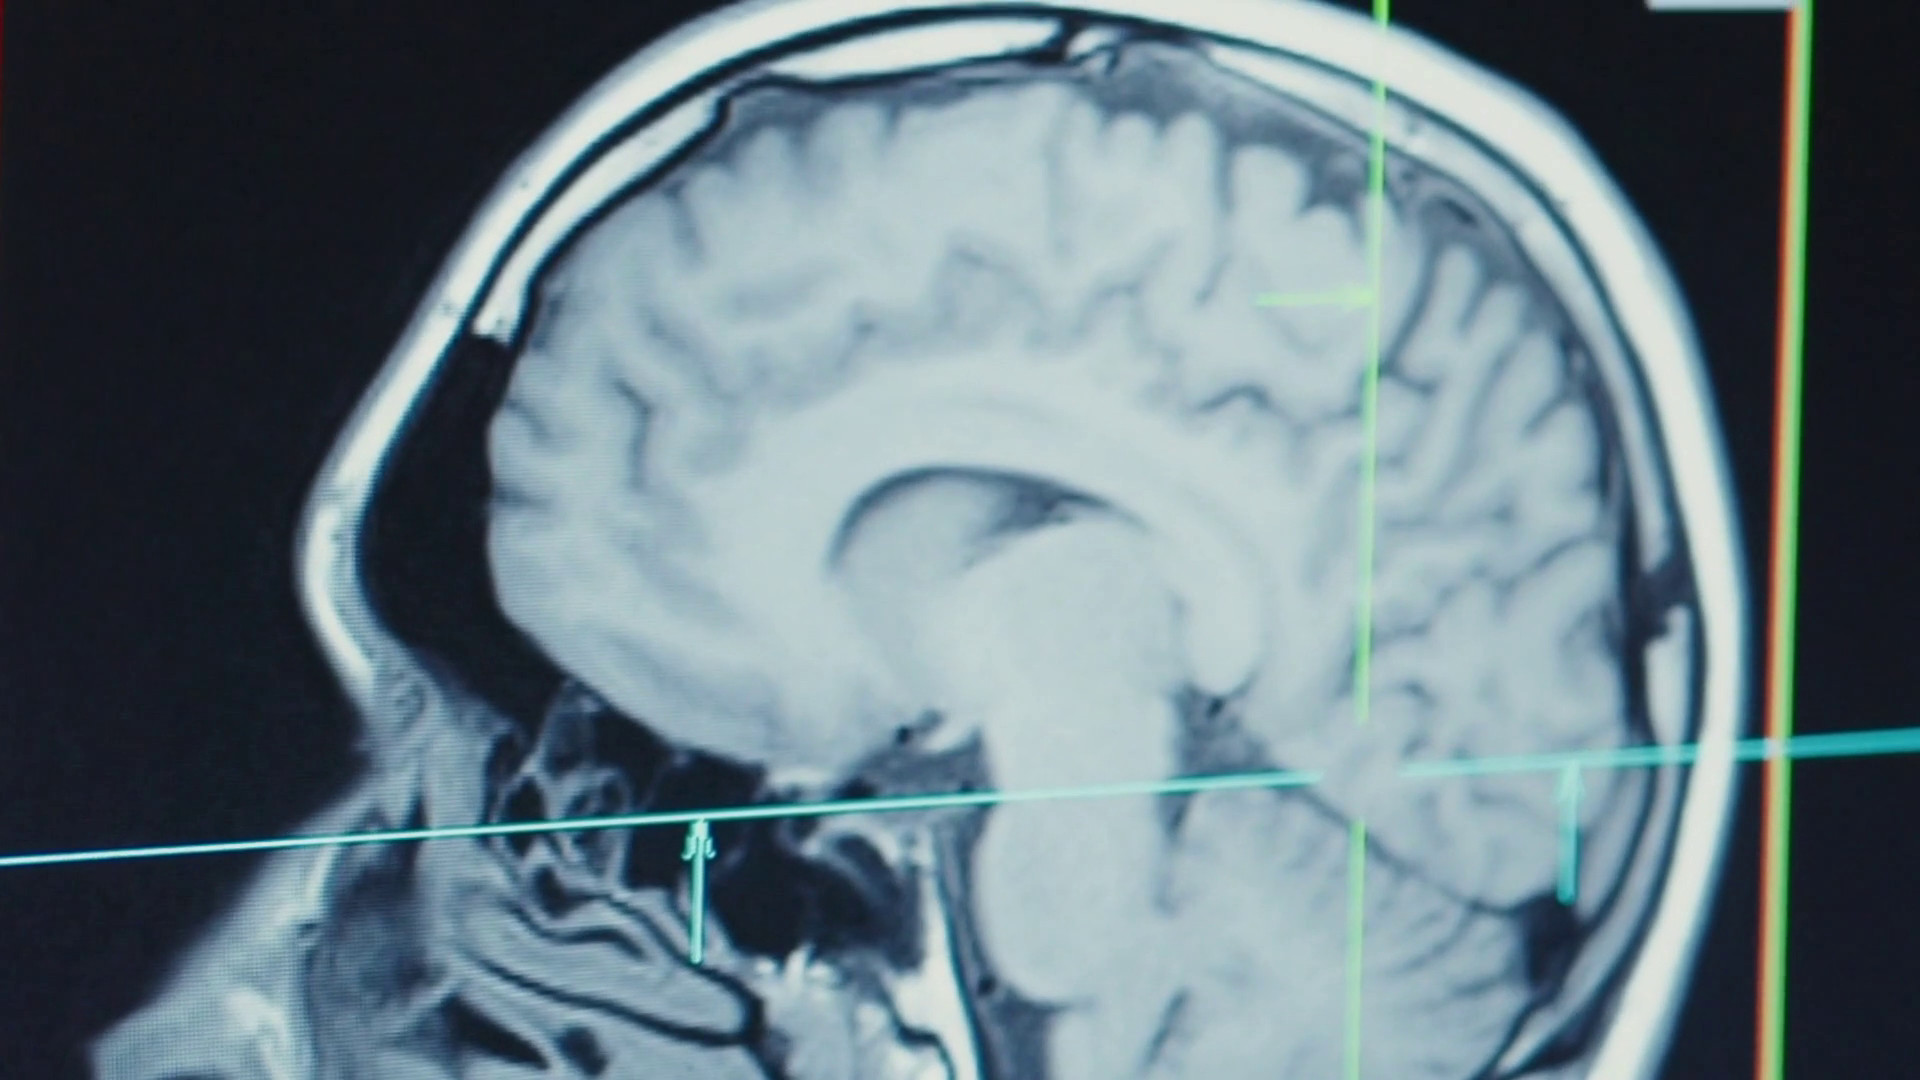

FIRENZE (ITALPRESS) – Il Parkinson è la seconda malattia neurodegenerativa più diffusa al mondo. È una patologia complessa, causata dalla progressiva morte di alcune cellule cerebrali che producono dopamina, un neurotrasmettitore fondamentale per il controllo dei movimenti. I principali sintomi motori includono tremore, rigidità muscolare, lentezza nei movimenti e disequilibrio. Un modello di cura innovativo nato a Firenze è Casa Parkinson, situato all’interno del presidio socio-sanitario Canova. Frutto della collaborazione tra l’Azienda USL Toscana Centro e la Fondazione Fresco Parkinson Institute, il centro si propone come un punto di riferimento per le persone che convivono con la malattia di Parkinson e per le loro famiglie.